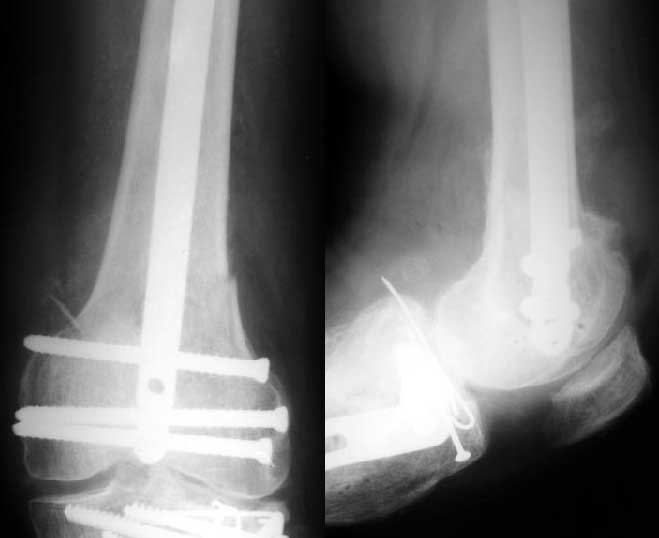

Sorry but I've just prepared postop images - attached. A solid 13 mm nail was used. A few degrees of recurvation appears to be which i missed on image intensifier. I'm still uncertain about

advantages/disadvantages of ante/retrograde nailing for such fractures.

The fixation as you have done is excellent. The locking screws on either side of the # are so apart. When we put in a supracondylar nail thro a keyhole incison in the knee, the locking bolts will be nearer the # and will be more stable allowing him to bear wt early. That was the reason the supracondylar nail was innovated. The locking is done by jig and no freehand method saving time.

The antegrade nail in the case shown is probably into the knee joint slightly.

TAC> The antegrade nail in the case shown is probably into the knee joint slightly.

Not in this case. Though i have a couple of similar cases with 3-4 mm prominince of the nail - looks asymptomatic or covered by pre-existing problems.